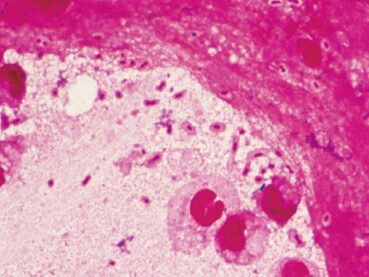

肺炎が疑われた患者の喀痰の Gram 染色標本を示す。分離菌はブドウ糖を発酵し、オキシダーゼ試験と運動性は陰性であった。考えられるのはどれか。

1. Acinetobacter baumannii

2. Klebsiella pneumoniae

3. Mycoplasma pneumoniae

4. Pseudomonas aeruginosa

5. Streptococcus pneumoniae